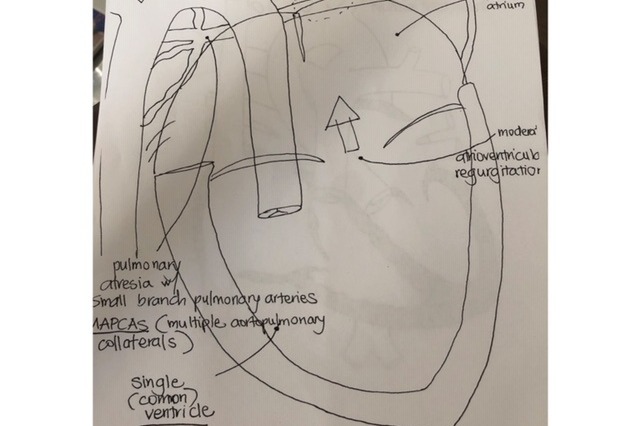

Hi my name is Melissa. Anthony Jr. or as we like to call him Baby AJ, was diagnosed with two very rare heart defects in my womb during our anatomy ultrasound at 19 weeks. Initially I was being cared for at CHOC St Joseph but was referred to Stanford Hospital as they specialize in the heart surgeries Baby AJ will need in his first years of life. We fought with insurance and after several denials and appeals we got the approval to deliver at Stanford. Because of his heart conditions the doctors are unable to give us a prognosis after his birth. In Baby AJ's case it's not a matter of if he will need heart surgery but when. There are about 3 things that they are looking for once baby AJ is born that will possibly need surgery right after birth; pulmonary collateral vessels, valve leakage, and possible anomalous pulmonary veins. Best case scenario is that Baby AJ will be stable after birth, he can wait to have surgery and we will return to Stanford in a couple of months. Worst case scenario is that AJ is not be able to tolerate all the heart complications he has and he will pass at birth, since he will now be cut from my umbilical cord and forced to use his own body and muscles to stimulate his heart. And then there are all the in betweens from those two scenarios. From the beginning we have been told to prepare for the worst, prepare to let Baby AJ go at birth, and really any chances of him making it is a miracle and them being very optimistic. A lot of my questions and wanting to know what to expect for Baby AJ is uncertain until he is born, even if Baby AJ is stable he will be undergoing many surgeries his first years of life and I am told the quality of his life may also be poor. I'm grateful to have been able to know about Baby AJ's heart condition so early on so my family and I can prepare ourselves mentally, emotionally, physically, spiritually, and financially.